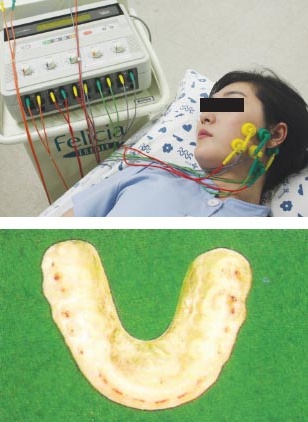

턱관절장애의 진단에는 측두하악장애 분석검사(간이평가,포괄적 병력조사, 포괄적 신체검사), 방사선학적 검사가 주로 진행되며 필요에 따라서는 전산화 단층방사선 검사(CT), 자기공명영상(MRI), 핵의학 검사(bone scan) 등도 시행할 수 있습니다. 턱관절 장애의 치료방법에는 물리치료, 약물요법, 교합 안정장치 치료, 보톡스 주사치료, 턱관절세정술을 비롯한 외과적 치료 등이 있습니다.